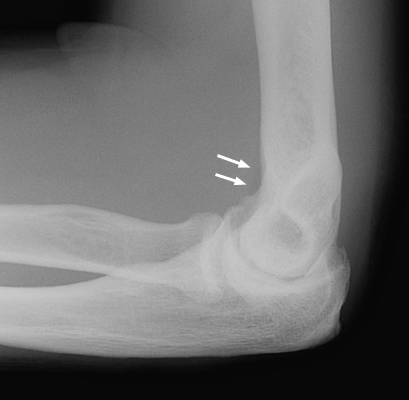

A. Normal lateral radiograph of the elbow. B. Plain film radiograph of the lateral elbow which reveals the classic elbow fat pad sign. This is an invaluable soft tissue finding in cases of intra-articular injury of the elbow. Fat is normally present within the joint capsule of the elbow, but outside the synovium. Typically "hidden" in the concavity of the olecranon and coronoid fossae, the fat is usually not visible on the lateral radiograph. However, injuries that produce intra-articular hemorrhage cause distension of the synovium and forces the fat out of the fossa, producing triangular radiolucent shadows anterior and posterior to the distal end of the humerus. When present in a patient with a history of acute trauma to the elbow, the fat pad sign indicates the presence of an intra-articular hemorrhage, which in turn is often associated with an intra-articular skeletal injury (usually the radial head in an adult).

Normal lateral rlbow - Click on the image for a larger versionALateral elbow - Click on the image for a larger versionB